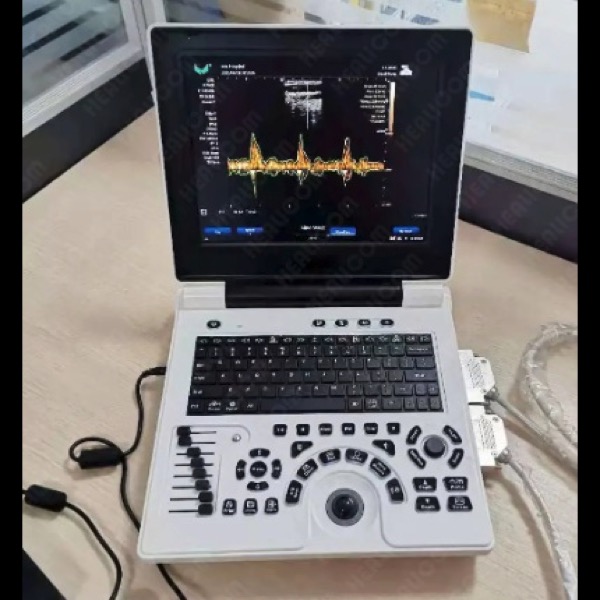

Écran couleur haute résolution de 12 pouces, 2 ports Sondes activés.

Modes d image :B,B/B,4B,B+M,CFM,B+CFM,PDI,B+PDI,PW

Applications cliniques : Abdomen, cardiologie, obstétrique, gynécologie, urologie, pédiatrie, petits organes,cardiaque.

Technologie imagerie:THI

Batterie rechargeable 3200mAh

Interfaces,HDMI,VGA,DICOM,USB,sortie video

Echelle de gris 256 niveaux